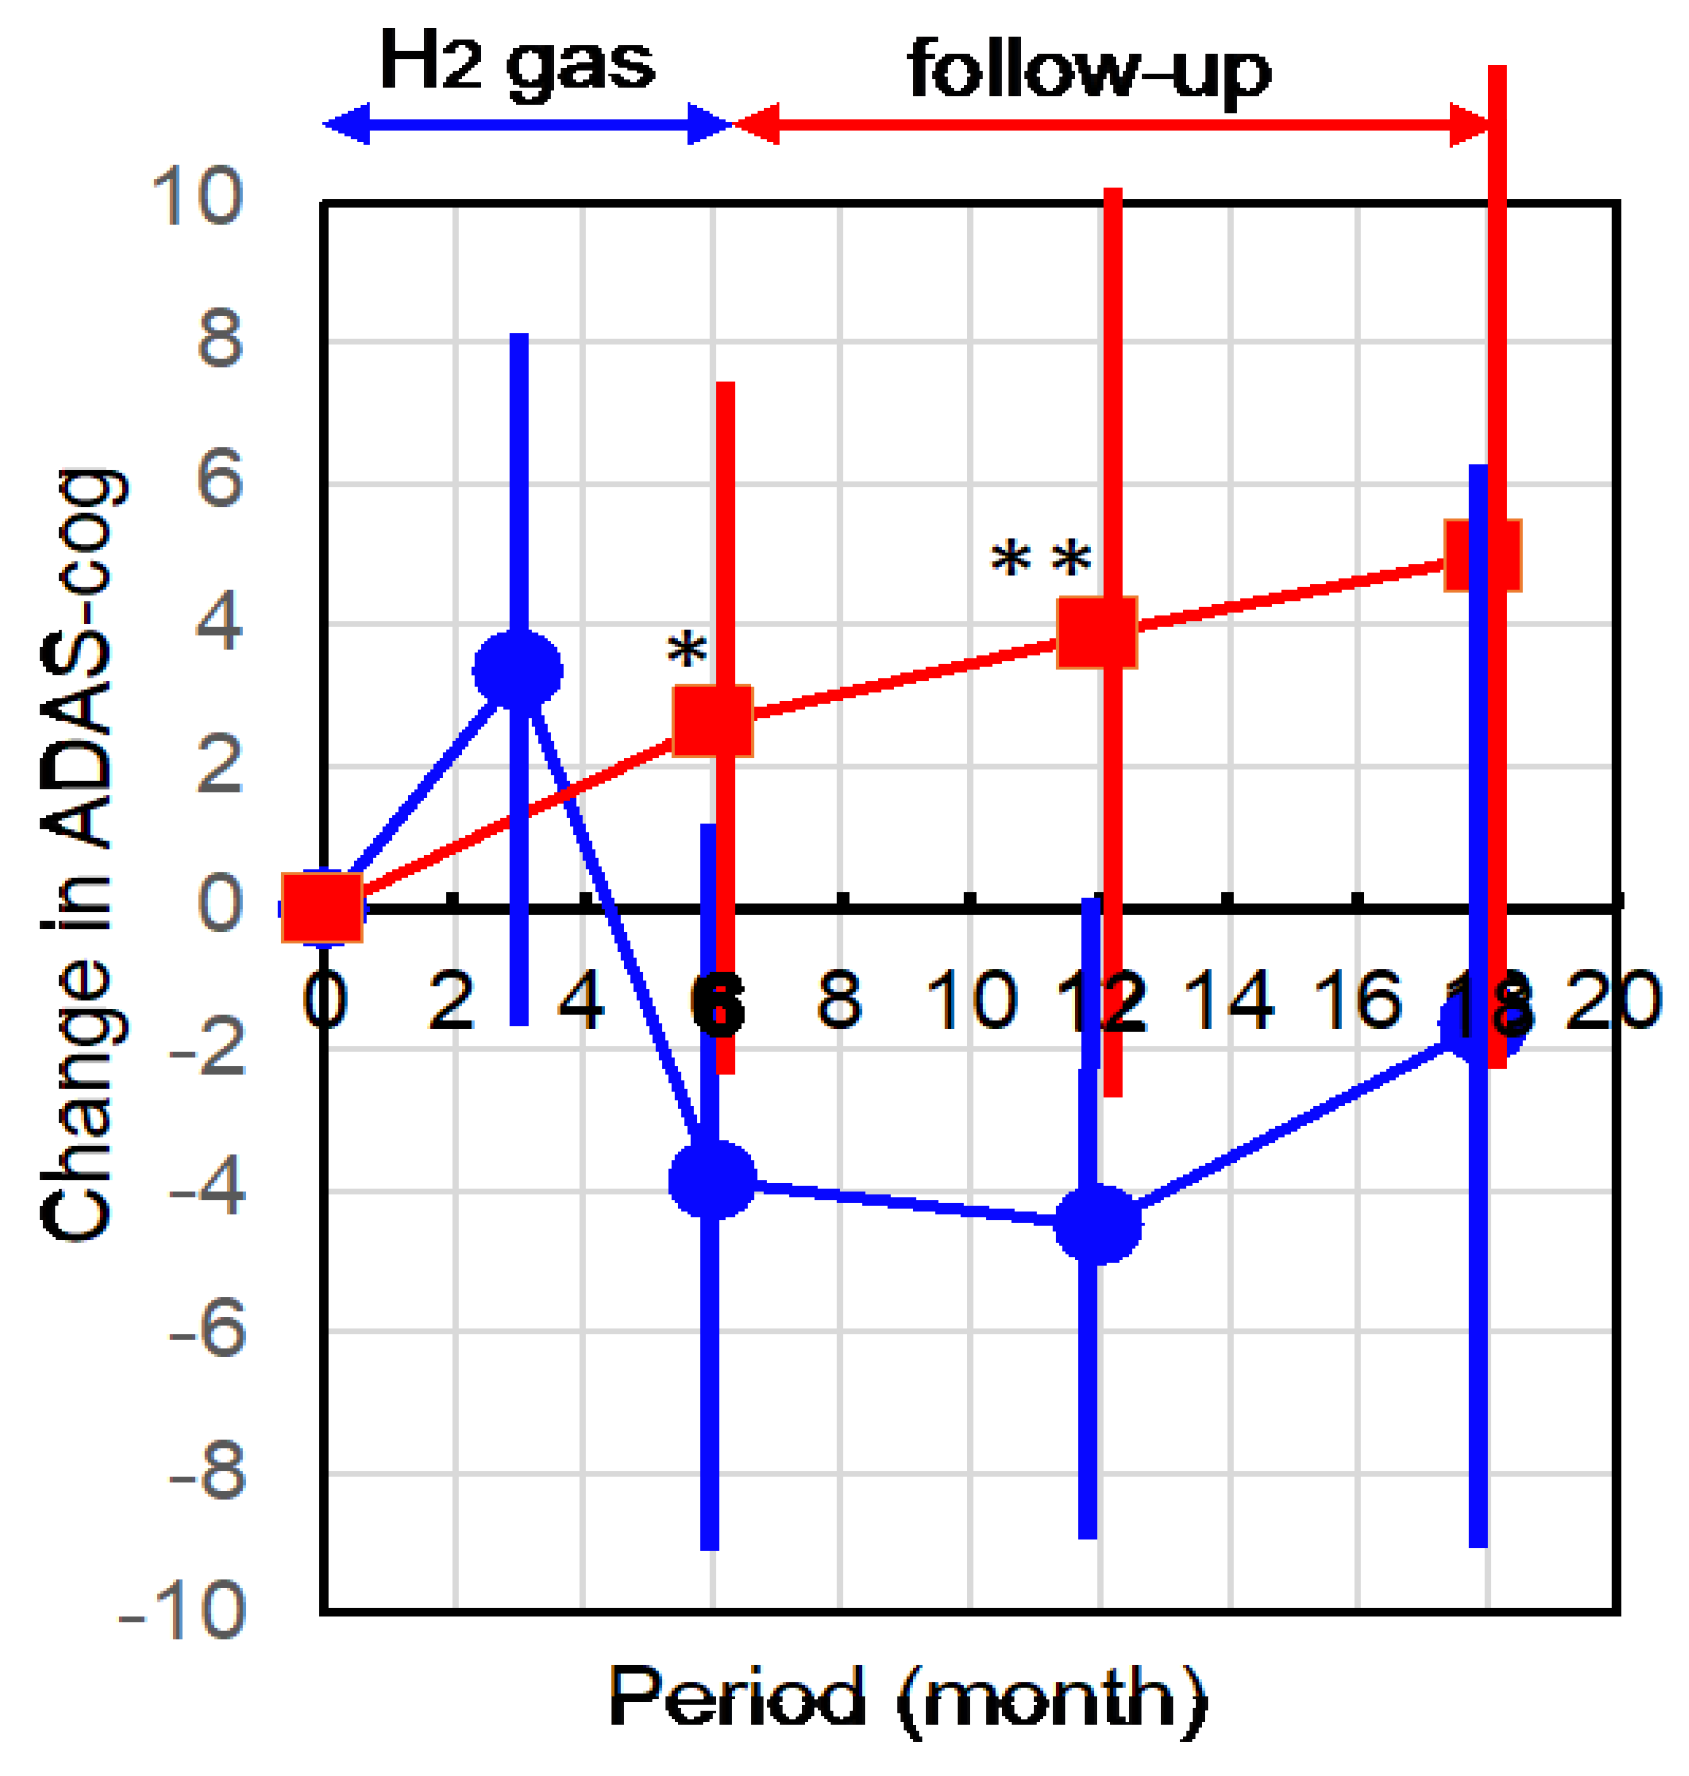

2.1. Hydrogen Treatment Improved AD as Assessed by ADAS-cog

4.5. ADAS-cog Examination

4.6. Measurement of the Integrity of Neurons by Diffusion Tensor Imaging

4.7. Statistical Analysis